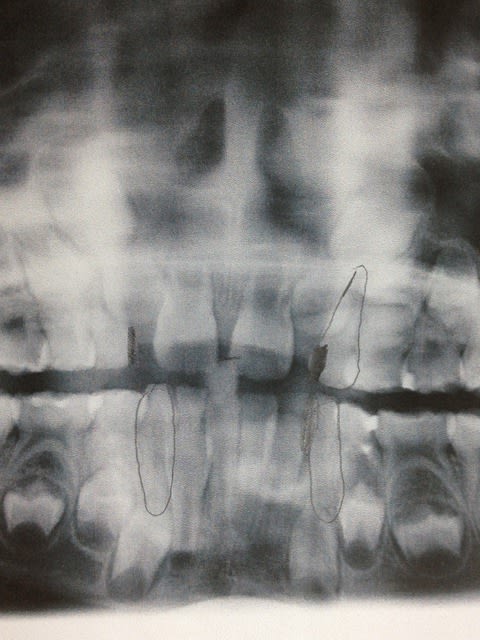

Bonjour! Enfant de pas encore 7ans présentant une DDM.L'ortho me demande d'extraire 53,63,73,83 (c'est la mode dans mon coin!)car manque de place pour la venue de la 12 et 22.Je trouve cela particulièrement traumatisant pour une petite fille de cette age.Ne peut-on pas selon vous passer par d'autres solutions en commençant par exemple à reserrer 11 et 21.

Ci joint la pano et merci pour vos réponses

Quelle solution pourrait-on bien proposer avec seulement une panoramique comme ça ?